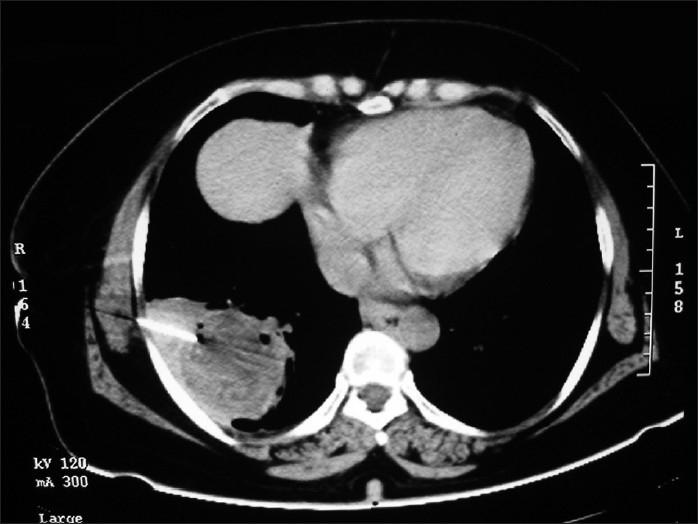

A 60-year-old female presented with pneumonitis of right lower zone. CT scan revealed mass like lesion with multiple air pockets. FNAC and ultrasound confirmed the diagnosis as isolated active pulmonary hydatid cyst, which is not common finding in adult population.

一名60岁女性因右下叶肺炎就诊。CT扫描显示有一个伴有多个气腔的肿块样病变。细针穿刺抽吸活检(FNAC)和超声检查确诊为孤立性活动性肺包虫囊肿,这在成人中并不常见。